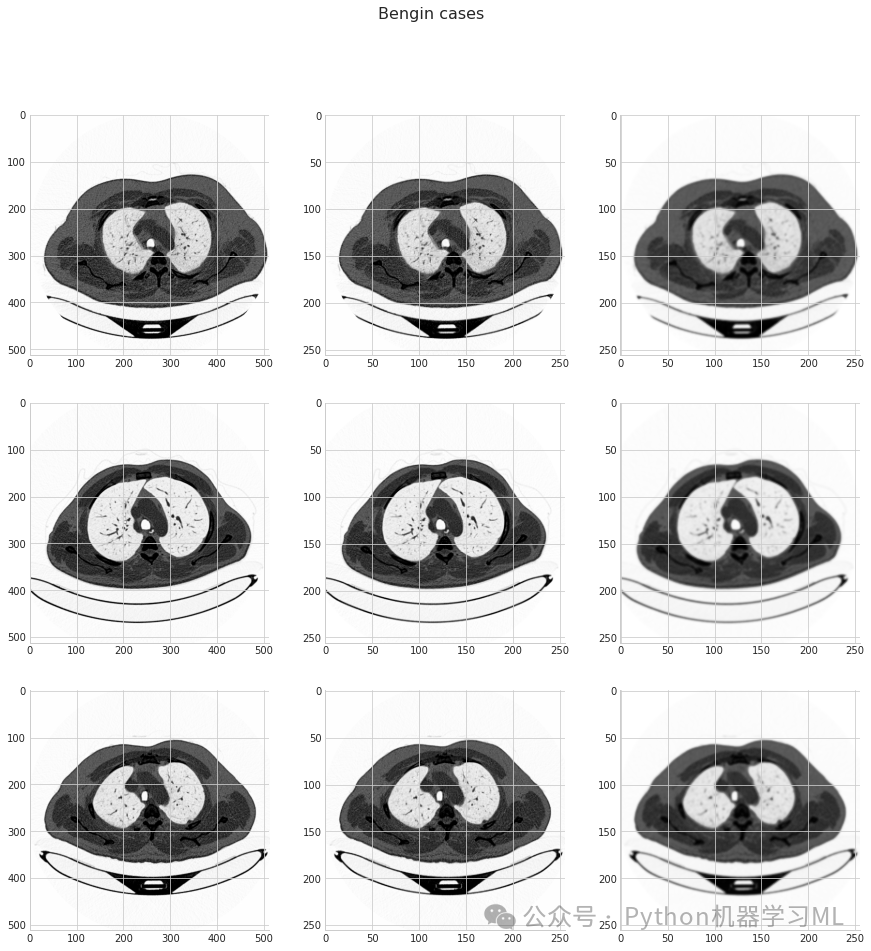

这段代码展示了每个类别的一个示例图像,帮助我们直观地了解数据内容。

pythonimg_size = 256 # 定义统一的图像尺寸为256x256

for i in categories: # 遍历每个类别

cnt, samples = 0, 3# 设置计数器和每类要显示的样本数

fig, ax = plt.subplots(samples, 3, figsize=(15, 15)) # 创建子图网格

fig.suptitle(i) # 设置图表标题为当前类别名称

path = os.path.join(directory, i) # 构建类别路径

class_num = categories.index(i) # 获取类别索引

for curr_cnt, file inenumerate(os.listdir(path)): # 遍历类别目录下的文件

filepath = os.path.join(path, file) # 构建文件完整路径

img = cv2.imread(filepath, 0) # 以灰度模式读取图像

img0 = cv2.resize(img, (img_size, img_size)) # 调整图像尺寸为256x256

img1 = cv2.GaussianBlur(img0, (5, 5), 0) # 对调整尺寸后的图像应用高斯模糊

ax[cnt, 0].imshow(img) # 显示原始图像

ax[cnt, 1].imshow(img0) # 显示调整尺寸后的图像

ax[cnt, 2].imshow(img1) # 显示高斯模糊后的图像

cnt += 1# 计数器加1

if cnt == samples: # 如果已显示指定数量的样本

break# 跳出循环

plt.show() # 展示所有子图

这段代码对每个类别展示了三个样本,并对每个样本展示了三种图像处理效果:原始图像、调整尺寸后的图像和高斯模糊处理后的图像。这有助于我们理解数据预处理步骤如何影响图像。